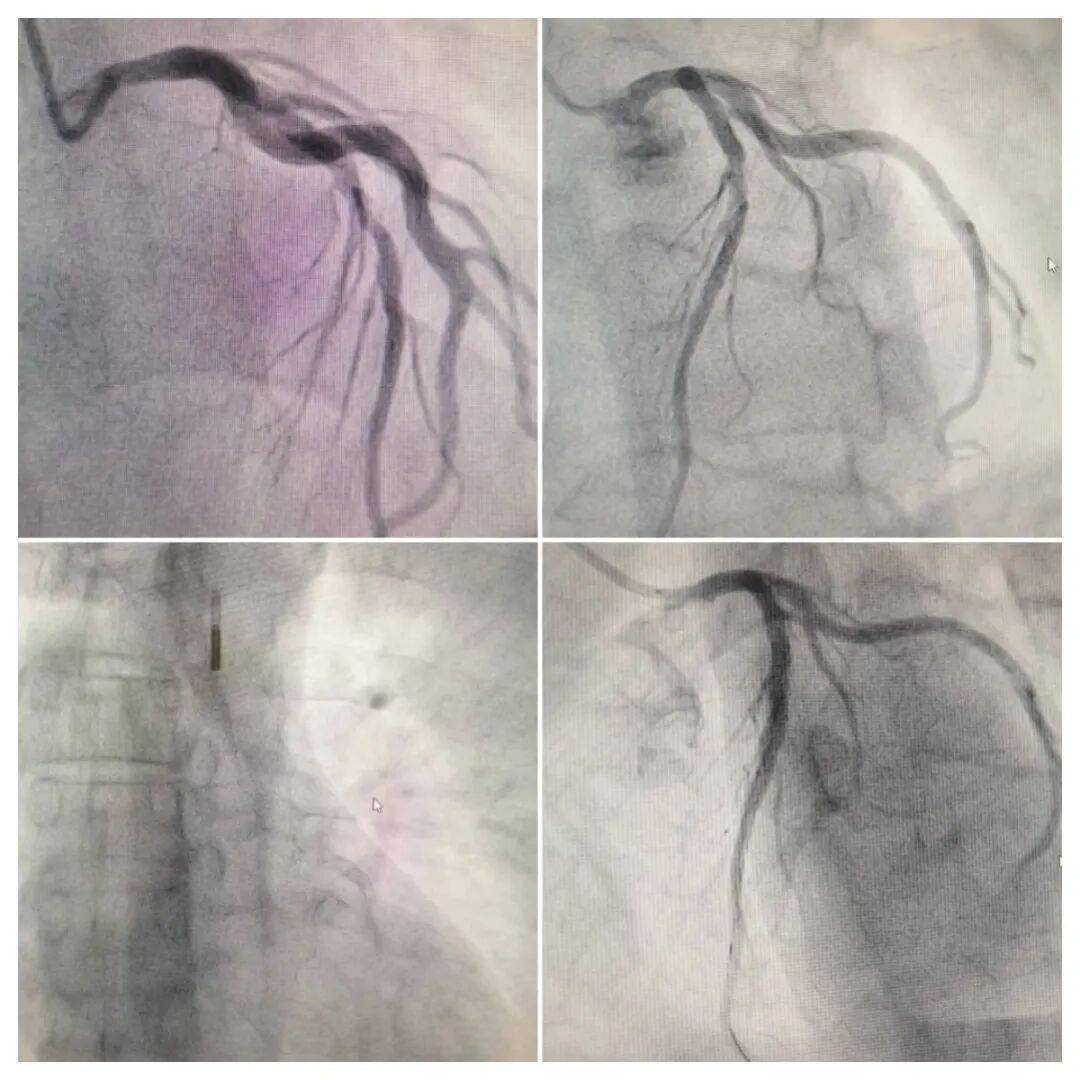

随后患者及时入院进行了冠脉造影检查,证实LAD近中段可见不稳定斑块影,偏心狭窄90%,TIMI血液仅3-级。经球囊扩张后送入IVUS见LAD近中段可见180-270°钙化环,最小管腔面积2.3mm²,斑块负荷80%。再通过棘突球囊扩张、支架置入等治疗,最终无残余狭窄,TIMI血流恢复到3级。术中还有个“插曲”。因斑块不稳定,术中一度出现低血压,伴胸闷,需要使用主动脉内球囊反搏IABP进行辅助循环。